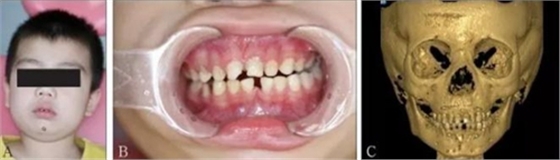

頜面部上下頜骨、顴骨及顴弓骨折、骨折片移位壓迫咀嚼肌群和下頜骨喙突,影響下頜骨的活動(dòng)而造成張口受限[10-12](圖 9、10)。

A:患者面像;B:口內(nèi)像;C:三維成像;D:全景片;E:冠狀位。

圖 9 面部外傷

左:顴弓骨折CT平掃;右:顴弓骨折CT三維成像。

圖 10 顴弓骨折